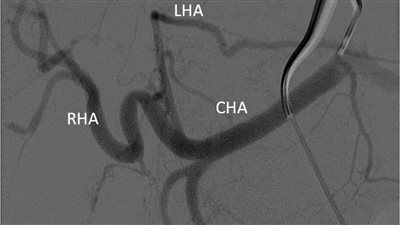

بنها الجامعي ينجح في حقن ورم كبدي كبير الحجم لمريضة من خلال قسطرة بالشريان

الأحد 06/فبراير/2022 - 11:06 ص